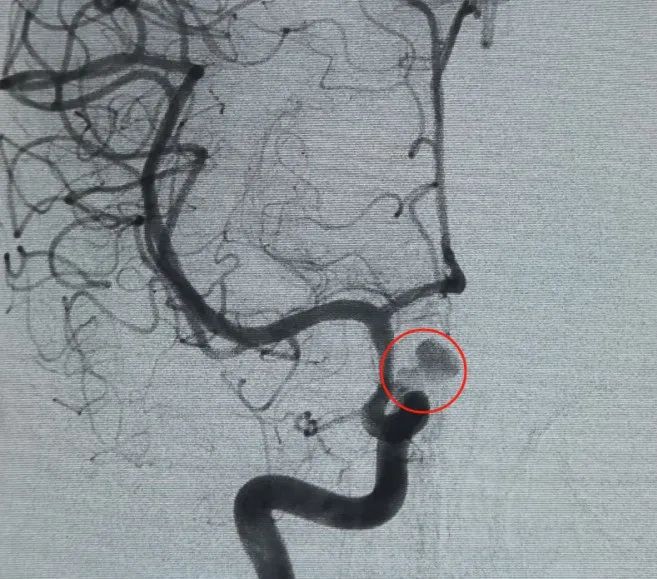

Диагноз: Аневризма левой внутренней сонной артерии сегмента C6 офтальмологической артерии

Сосудистый доступ был установлен через пункцию бедренной артерии, и Перденсатор®3D-катушка 6 мм × 20 см была впервые развернута для формирования корзины, обеспечивая стабильное расположение стены и надежную внутриаккулярную поддержку. За этим последовало введение перденсатора®3D-катушка 6 мм × 15 см для нарушения кровотока внутри лобулированного дочернего мешка.

Перфиллер®Расширяемая катушка 3 мм × 6 см и перфиллер®Затем была помещена расширяемая катушка 3 мм × 2 см, чтобы завершить окклюзию шеи. Впоследствии, Нува®Отвод потока (TJED-D-5.0-16) был доставлен и развернут через шейку аневризмы. Последующая ангиография как на передне-задних, так и на боковых видах подтвердила отличное покрытие, хорошее расположение стенок и четкую рентгеноконтрастность с заметной контрастной стагнацией.